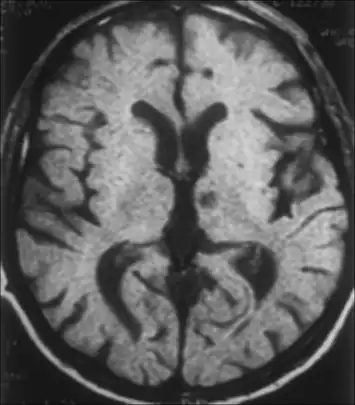

Left subthalamic nucleus stroke caused contralateral hemiballism.- Hyperglycemia-induced involuntary movements (in this case, not hemiballismus, but hemichorea (chorea of one side of the body) and bilateral dystonia) in a 62-year-old Japanese woman with type 1 diabetes.